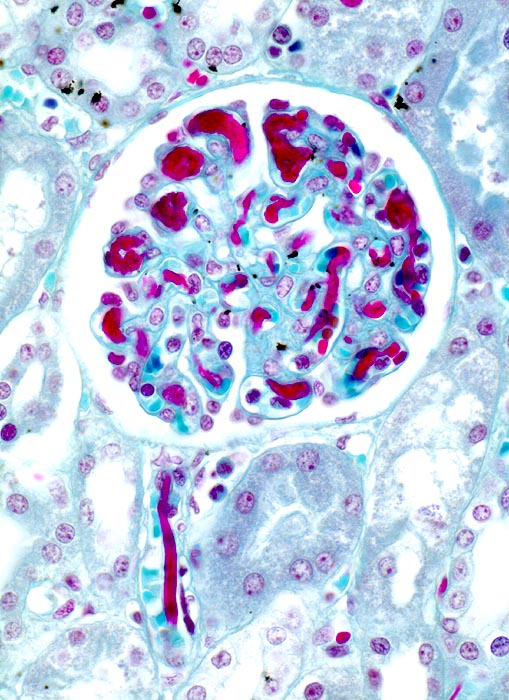

PathoPic ID 3530 - disseminierte intravasale Gerinnung

disseminierte intravasale Gerinnung

vaskulär / Durchblutungsstörung

Niere

Niere, Harnwege

Die Glomerulumkapillaren und das

Vas afferens sind angefüllt mit roten wurmförmigen Fibrinthromben.

Sepsis. Multiple Hämatome an druckbelasteten Hautlokalisationen. Akutes Nierenversagen.

Histologie

125